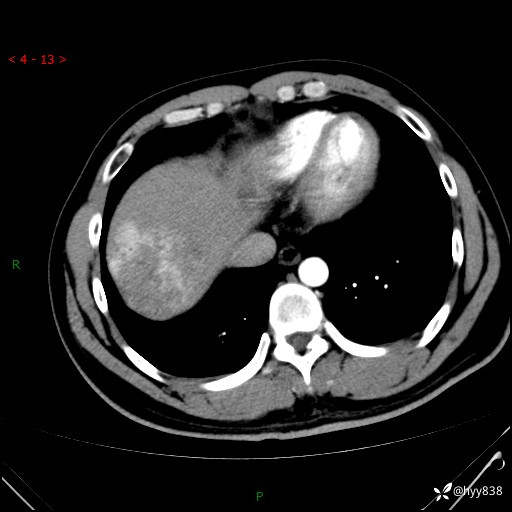

肝脏CT平扫

img